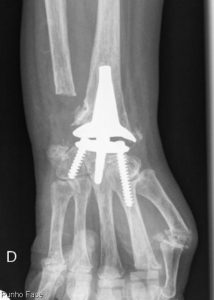

Foi com muito gosto que colaborei no tratamento de um doente com artrite do punho e efetuamos mais uma artroplastia total do punho.